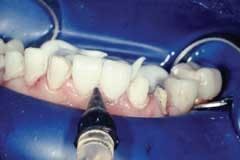

Rubber dam use is critical on mandibular teeth to isolate the lip and tongue and control moisture. Vanilla Bite (Discus Dental) was used to seal the lingual area (Fig. 1). Rubber dam use is also recommended for maxillary teeth. The preparations were cleansed with ConsepsisScrub (Ultradent) and a prophy cup (Fig. 2).

The resin cement is placed inside the veneers, and they are seated onto the preparations. With the smallest diameter tip (2mm) and the Optilux 501 Curing Light (Kerr), the veneers are tacked for five seconds in the middle third. Avoid polymerization of the margins or the cleanup of excess cement will become more time-consuming. Using a rubber-tip stimulator, microbrushes, and Glide dental floss, remove excess cement along the margins (Fig. 8).